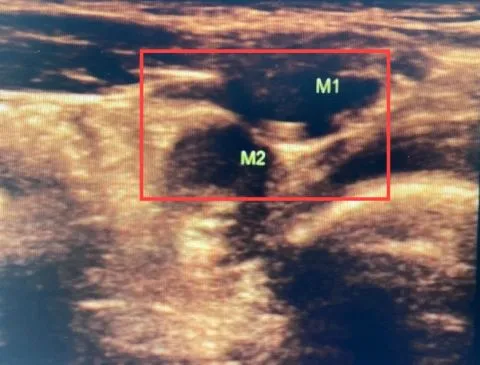

接诊的徐晓龙副主任医师仔细查体,发现小飞的左侧睾丸位于左侧腹股沟上段,而右侧睾丸在腹股沟区及阴囊均未触及,考虑小飞右侧睾丸位于腹腔内或腹膜后。在给小飞进行腹部超声检查后,徐晓龙副主任医师发现小飞右侧的“蛋蛋”极有可能异位到左侧腹股沟内环口处。入院后,进一步进行盆腔MR扫描,小飞左侧腹股沟区存在两个异常信号影,徐晓龙副主任医师判断小飞左侧隐睾、右侧睾丸异位的可能性极大。

MR显示左侧腹股沟区有两个异常信号影